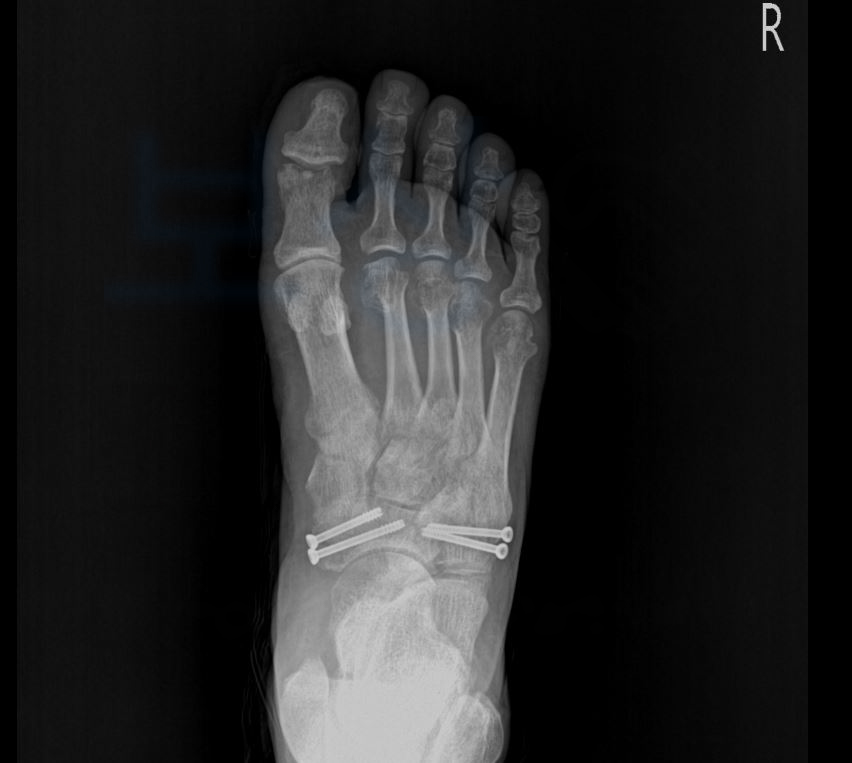

위 인정된 상병명을 보시면 **우측 2~5족지 개방성 골절 **및 발등의 골절 모두 인정받았죠. 산재 신청이 무사히 완료된 의뢰인은 휴업급여도 지급받으시며 산재 요양을 받게 되었는데요, 안타깝게도 엄지 발가락의 골절 부위에 골수염이 발생하여

1족지 즉 엄지발가락을

절단술을 시행하셔야 했습니다. 😭